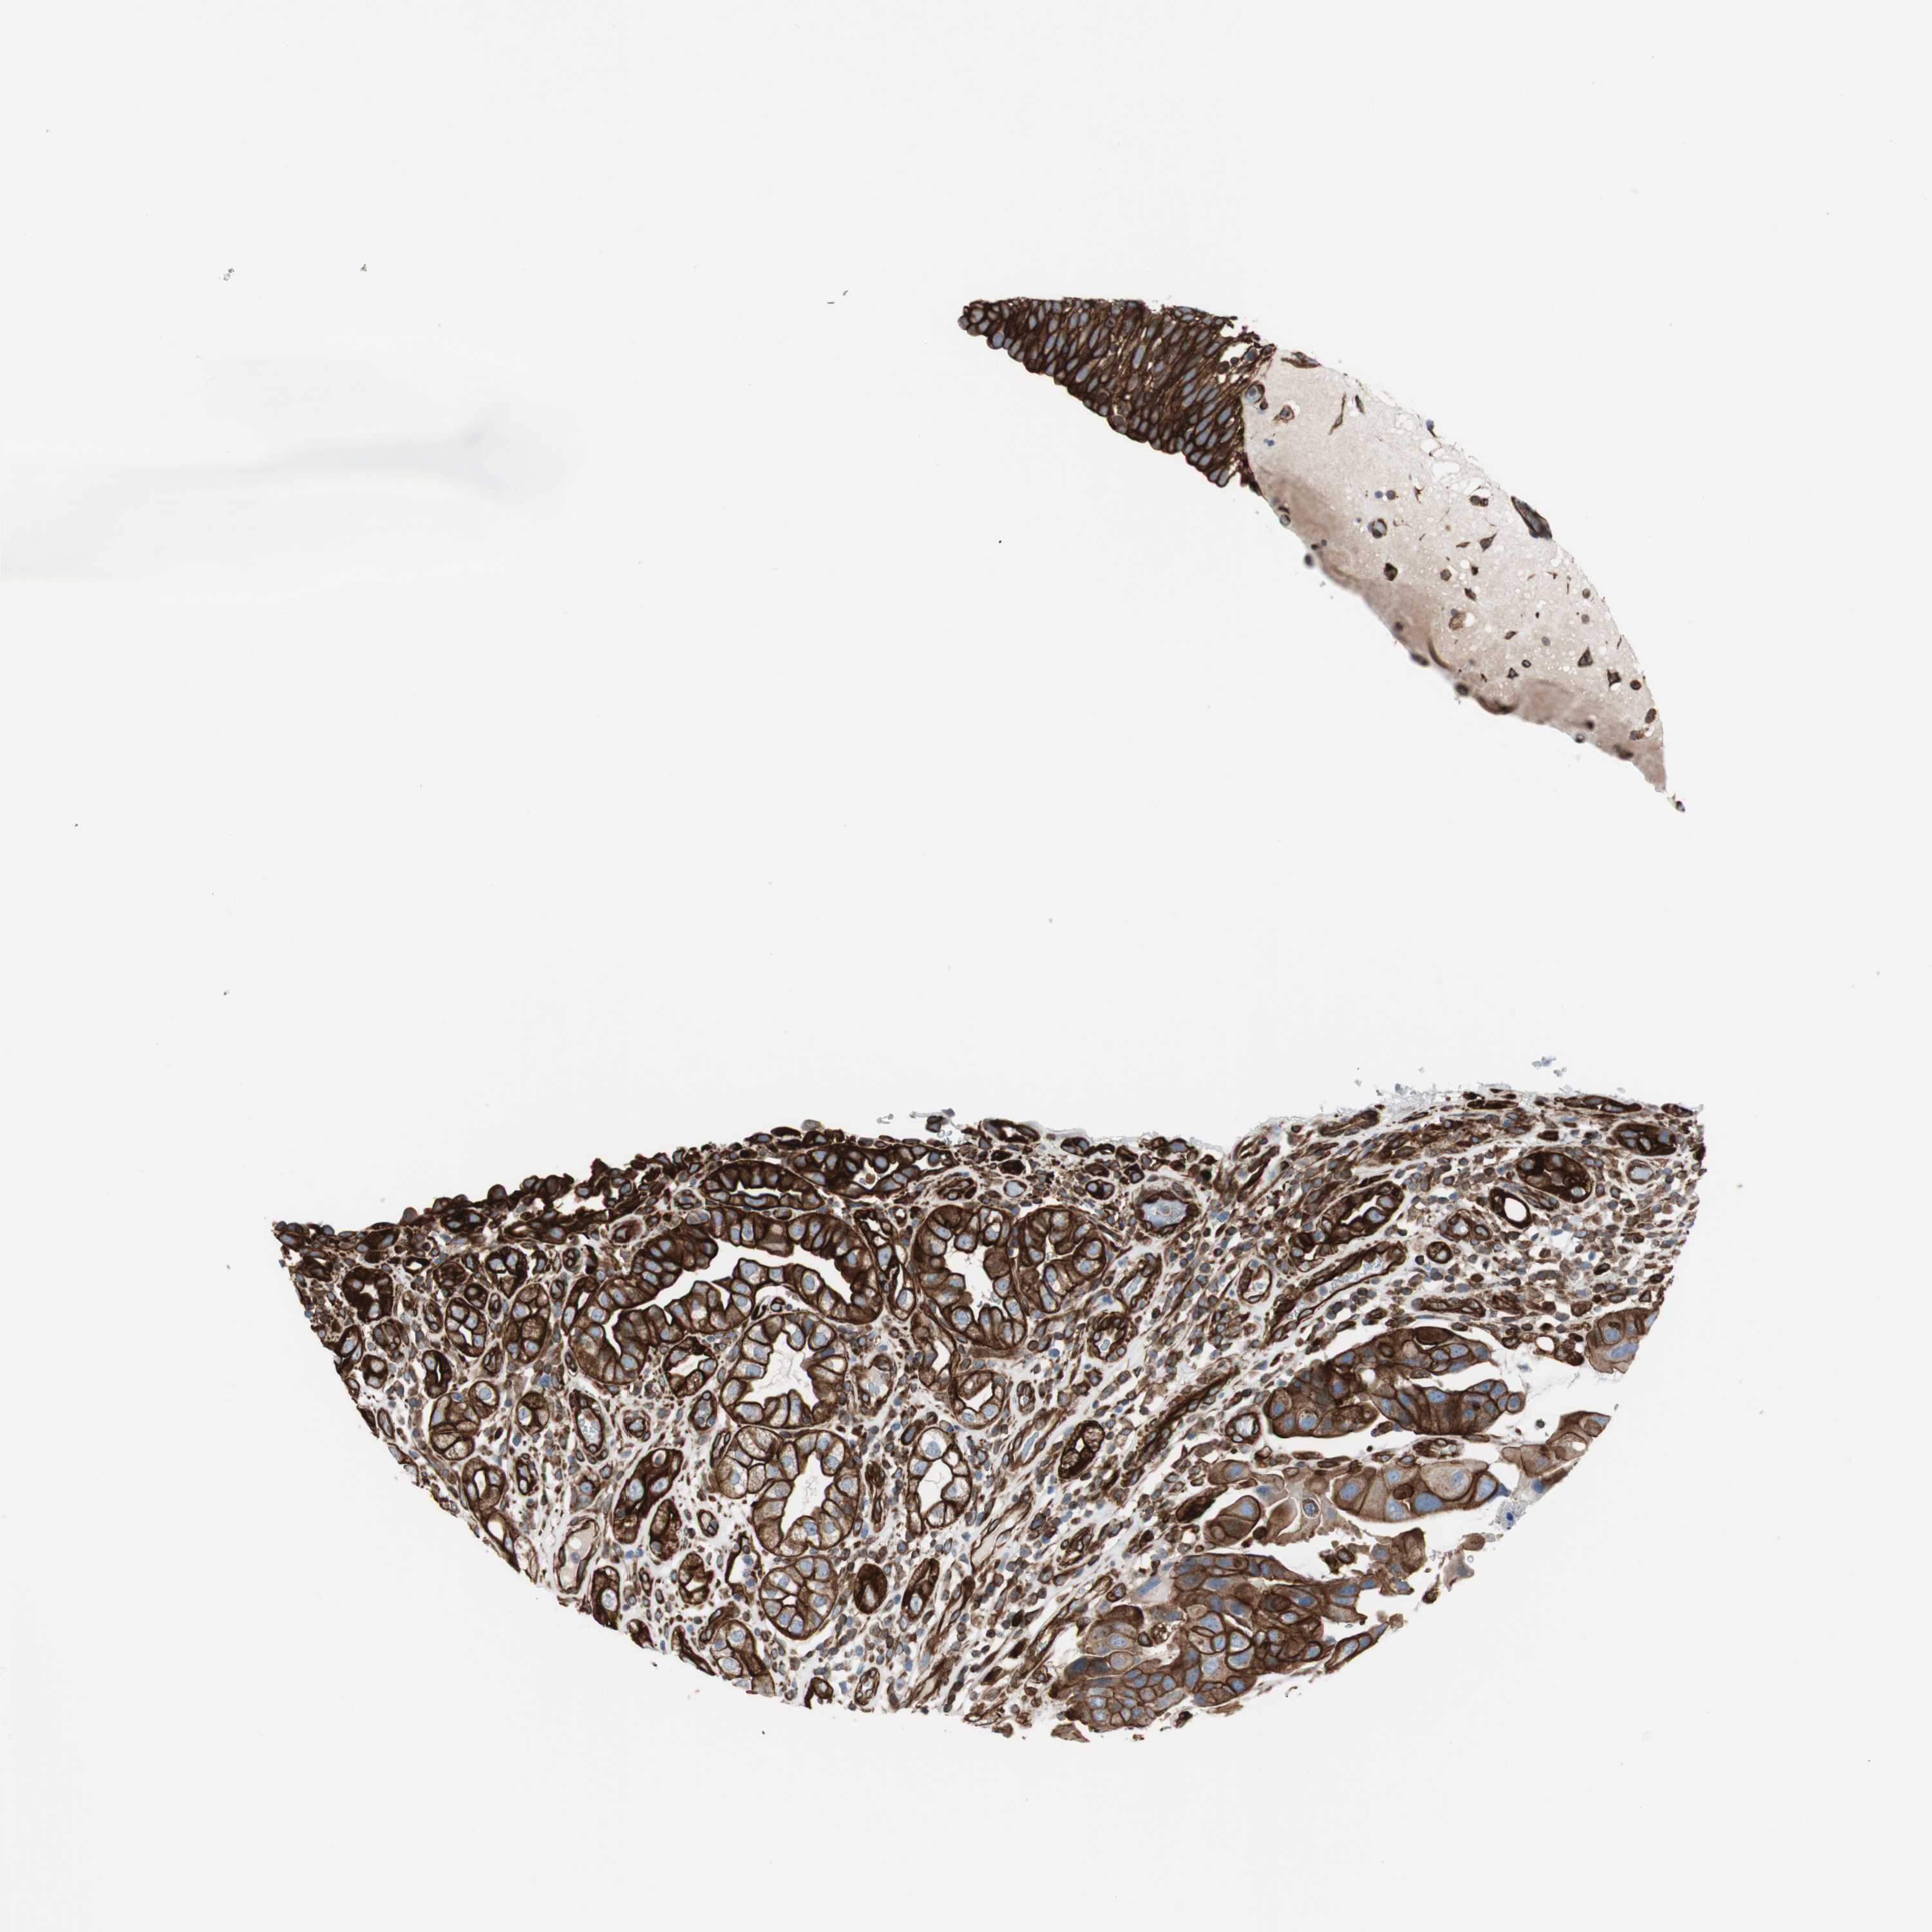

UROTHELIAL CANCER - Protein expressioni

A mouse-over function shows sample information and annotation data. Click on an image to view it in a full screen mode. Samples can be filtered based on level of antibody staining by selecting one or several of the following categories: high, medium, low and not detected. The assay and annotation is described here.

Antibody stainingi

Antibody staining in the annotated cell types in the current human tissue is reported as not detected, low, medium, or high, based on conventional immunohistochemistry profiling in selected tissues. This score is based on the combination of the staining intensity and fraction of stained cells.

Each image is clickable and will lead to virtual microscopy that enables deeper exploration of all samples and also displays staining intensity scores, fraction scores and subcellular localization as well as patient and tissue information for each sample.

Antibody HPA007342

Staining

High

Medium

Low

Not detected

Intensity

Strong

Moderate

Weak

Negative

Quantity

>75%

75%-25%

<25%

None

Location

Nuclear

Cytoplasmic/membranous

Cytoplasmic/membranous,nuclear

Urothelial carcinoma, Low grade